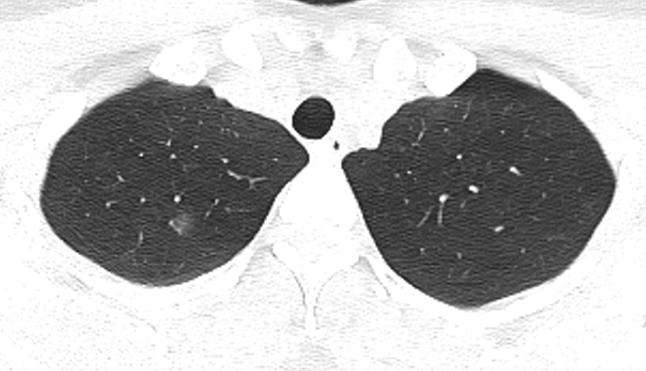

胸部CT示:双肺多发磨玻璃结节,左下叶背段散在实性结节,散在小空洞,部分支气管的管壁增厚,如下(图1~17)。